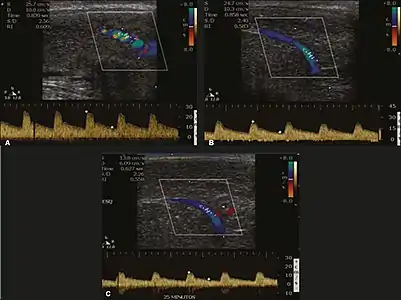

Erection can be induced by injecting 10–20 µg of prostaglandin E1, with evaluations of the arterial flow every five minutes for 25–30 min (see image). The use of prostaglandin E1 is contraindicated in patients with predisposition to priapism (e.g., those with sickle cell anemia), anatomical deformity of the penis, or penile implants. Phentolamine (2 mg) is often added. Visual and tactile stimulation produces better results. Some authors recommend the use of sildenafil by mouth to replace the injectable drugs in cases of contraindications, although the efficacy of such medication is controversial.[39]

Before the injection of the chosen drug, the flow pattern is monophasic, with low systolic velocities and an absence of diastolic flow. After injection, systolic and diastolic peak velocities should increase, decreasing progressively with vein occlusion and becoming negative when the penis becomes rigid (see image below). The reference values vary across studies, ranging from > 25 cm/s to > 35 cm/s. Values above 35 cm/s indicate the absence of arterial disease, values below 25 cm/s indicate arterial insufficiency, and values of 25–35 cm/s are indeterminate because they are less specific (see image below). The data obtained should be correlated with the degree of erection observed. If the peak systolic velocities are normal, the final diastolic velocities should be evaluated, those above 5 cm/s being associated with venogenic ED.[39]

Graphs representing the color Doppler spectrum of the flow pattern of the cavernous arteries during the erection phases. A: Single-phase flow with minimal or absent diastole when the penis is flaccid. B: Increased systolic flow and reverse diastole 25 min after injection of prostaglandin.[39]

Longitudinal, ventral ultrasound of the penis, with pulsed mode and color Doppler. Flow of the cavernous arteries at 5, 15, and 25 min after prostaglandin injection (A, B, and C, respectively). The cavernous artery flow remains below the expected levels (at least 25–35 cm/s), which indicates ED due to arterial insufficiency.[39]